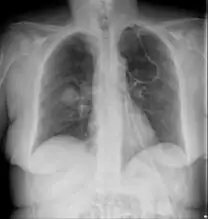

Chest X-ray: likely fungal infection left lung in an immunocompromised person -